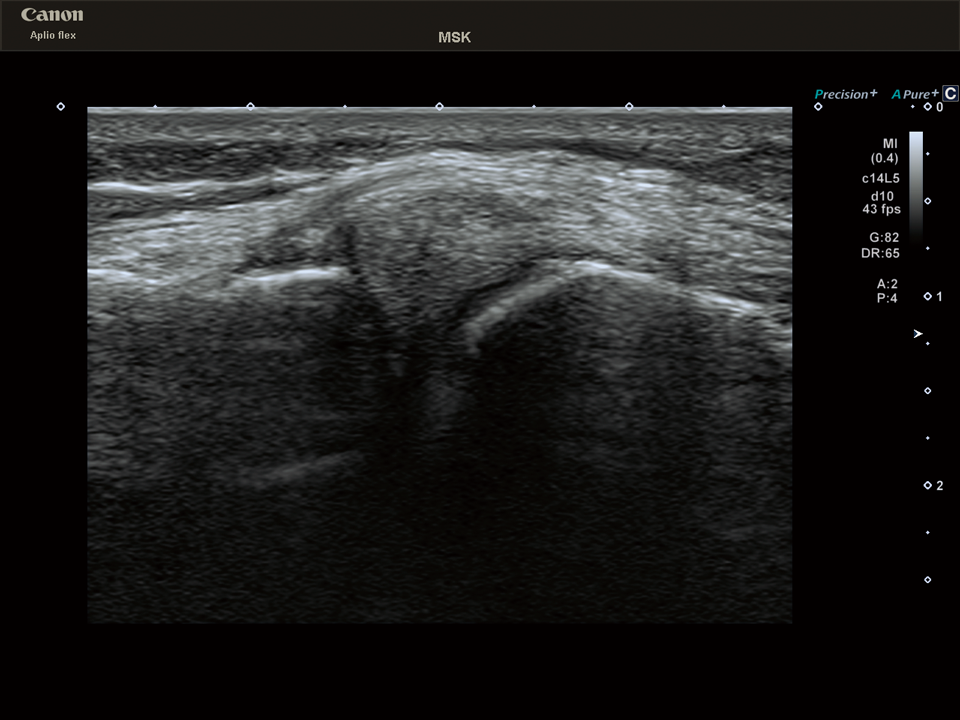

Precision Imaging

近接する超音波ライン信号を高速処理し、実質組織を均一かつ構造の境界を強調することで組織の視認性を高めます。

頸動脈 プラーク